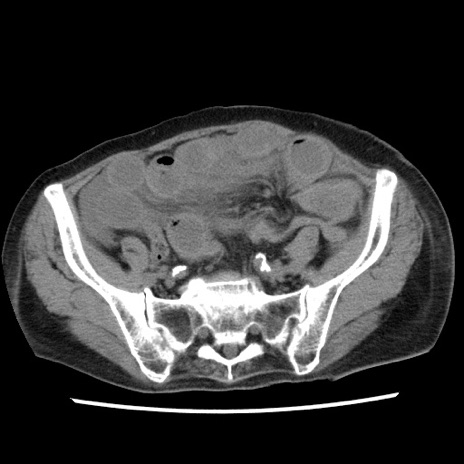

症例1(横断像)

症例

【症例】80歳代女性

【主訴】腹痛

【現病歴】8時間前から腹痛あり来院。

【既往歴】糖尿病、脂質異常症、子宮体癌にて子宮全摘術

【身体所見】意識清明・会話良好だが腹痛で苦悶様、全腹部にわたって反跳痛と圧痛あり

【データ】WBC 13600、CRP 0.14、LDH 224、CK 90